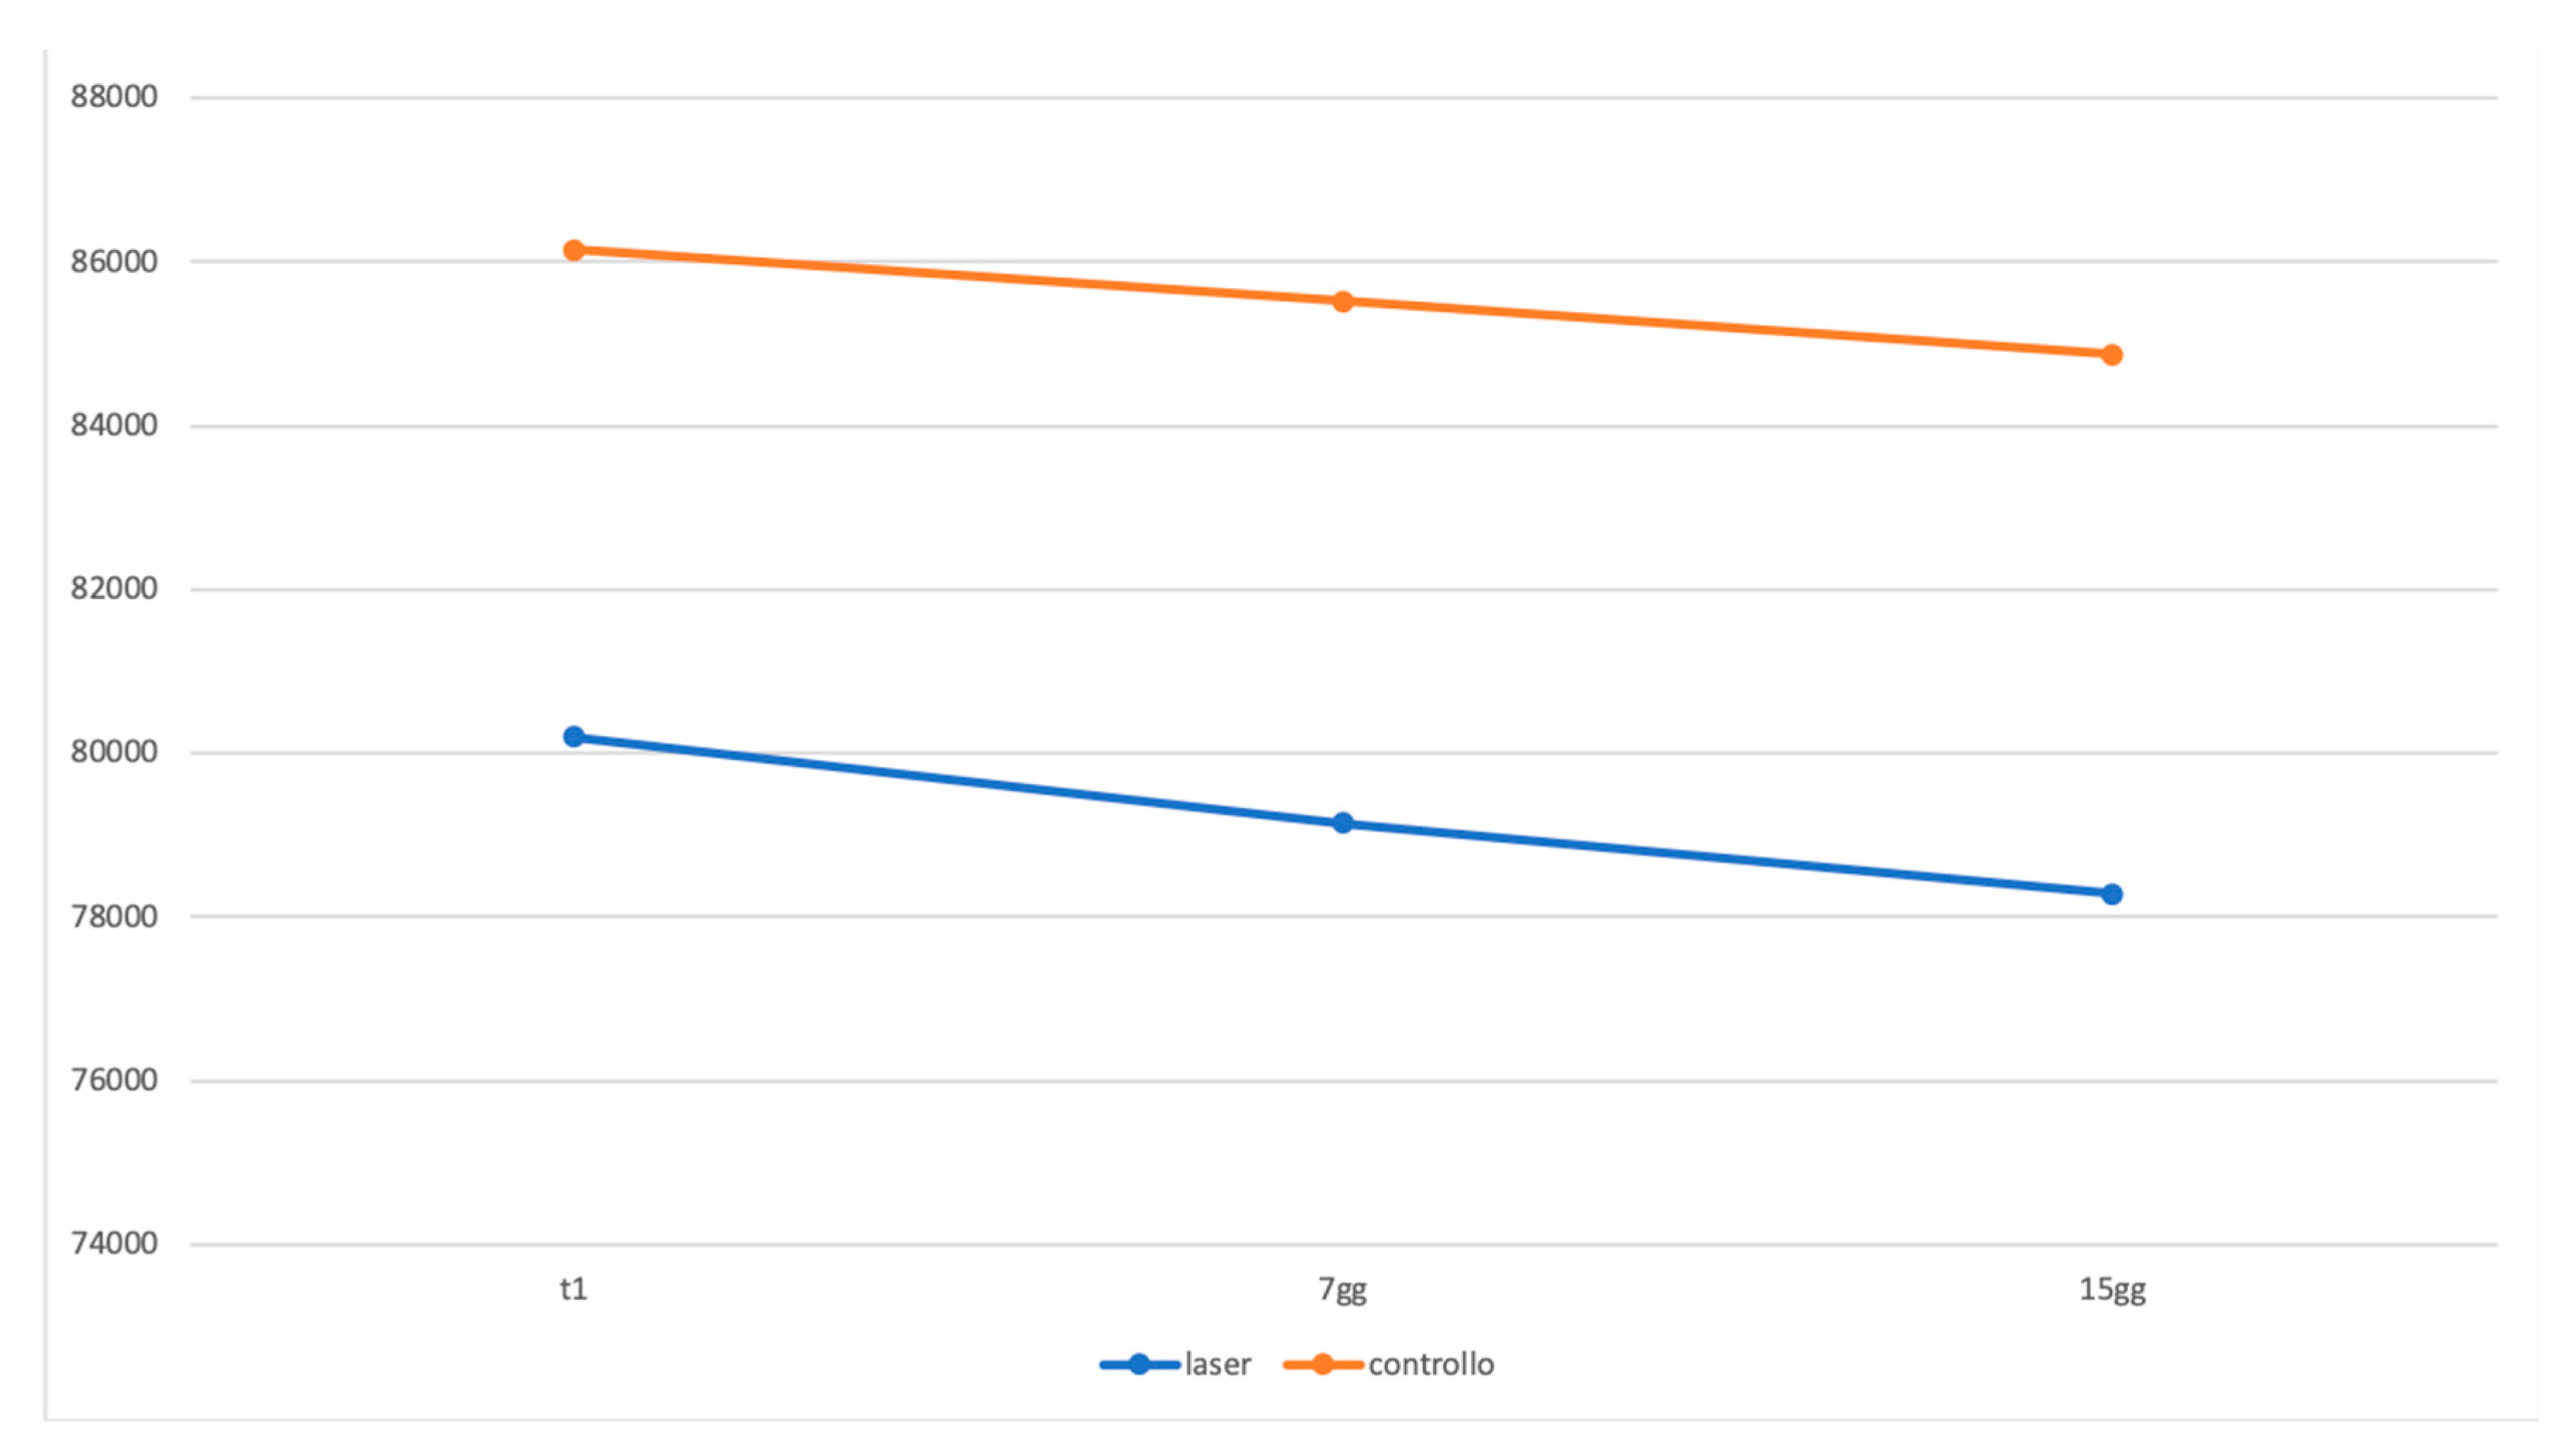

3. Results

4. Discussion